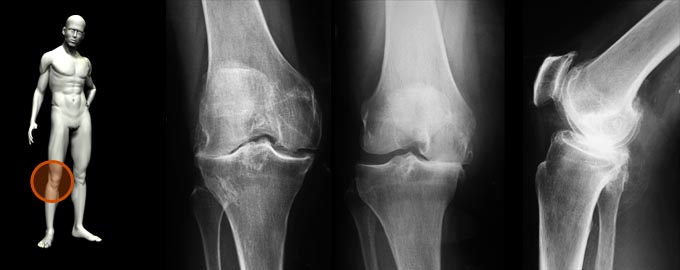

La Traumatología y Ortopedia, es una especialidad de la medicina, dedicada específicamente a las enfermedades del sistema musculo-esquelético.

• Enfermedades degenerativas por desgaste (secundarias a lesiones antiguas no tratadas adecuadamente o causadas por sobrecarga en el trabajo, por obesidad, etc.)

- Genu valgo

- Genu varo